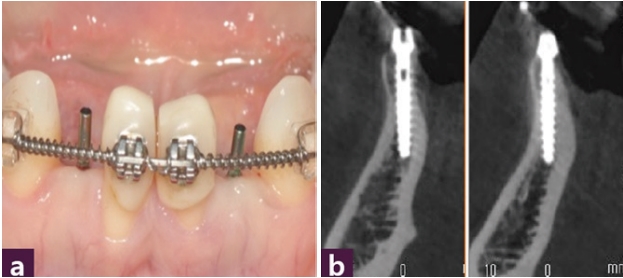

36세 여성 환자로 재보철을 하기 위하여 내원하였으나 공간이 충분치 않아 부분교정 후 임플란트 식립 계획을 세웠다 [그림 7].

임플란트 수술 시에는 Magic GPS를 이용하여 뼈 중앙에 MagiCore를 최소 침습적으로 식립하였다 [그림8].